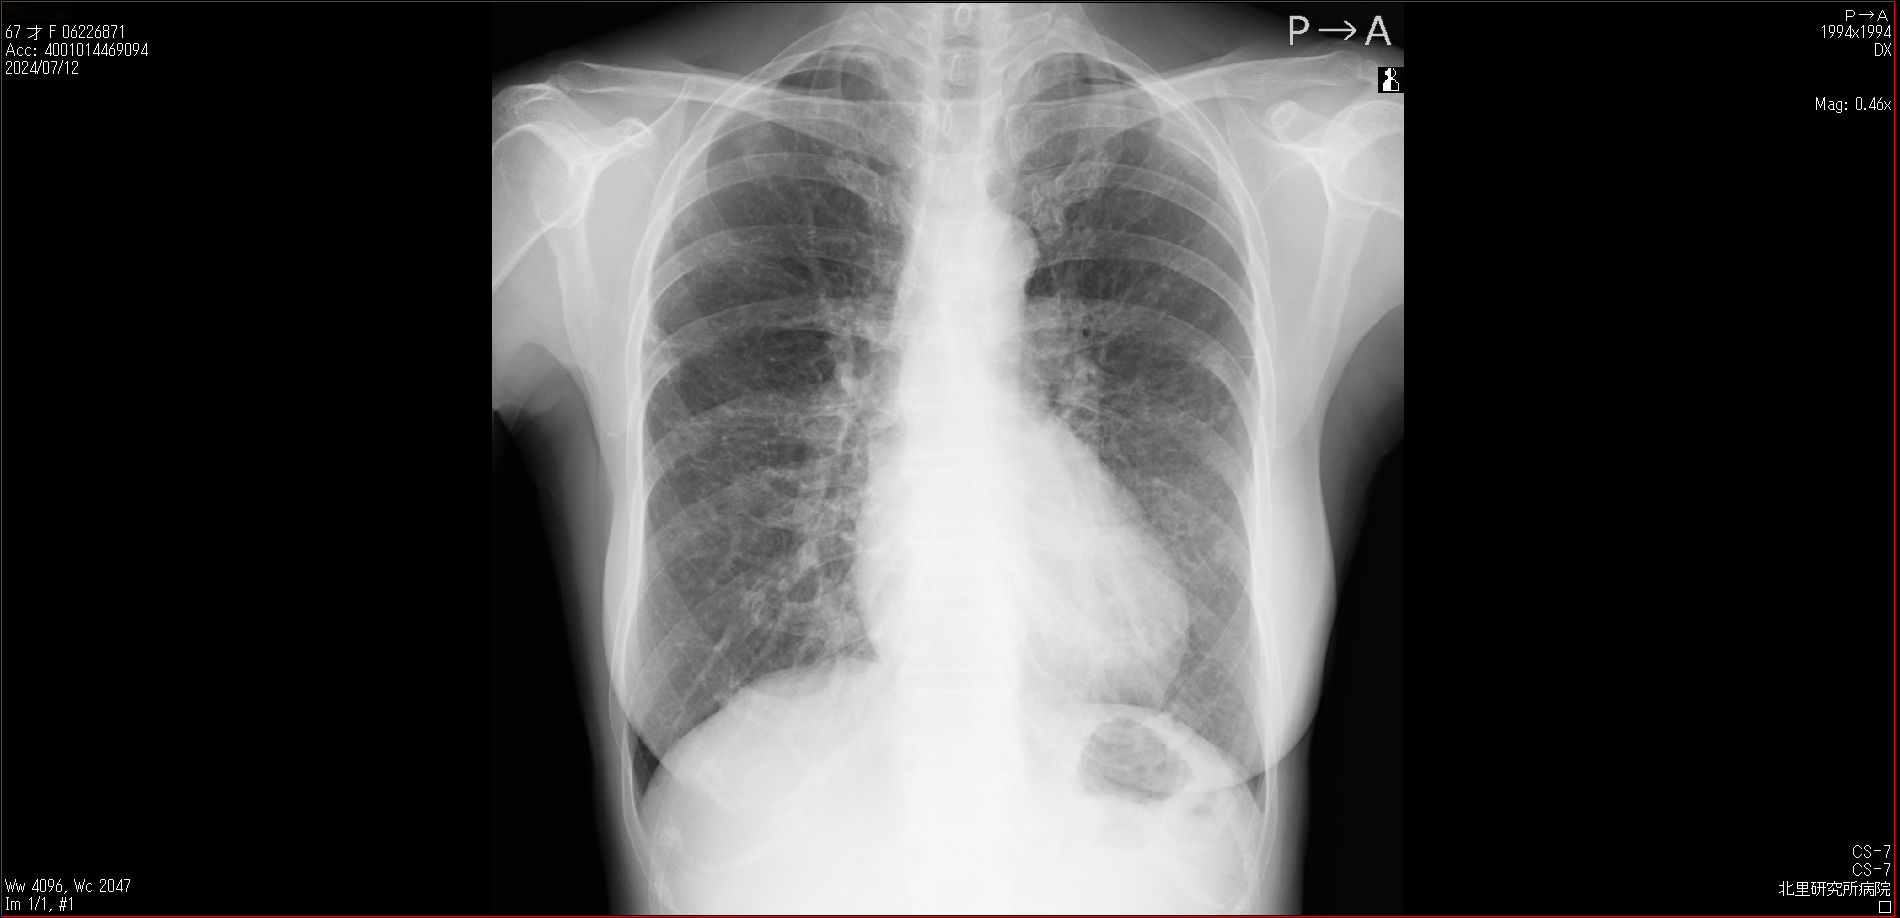

肺X線画像

2024

- 2024.07.12 転院後の要観察(2)(私立の病院Z)